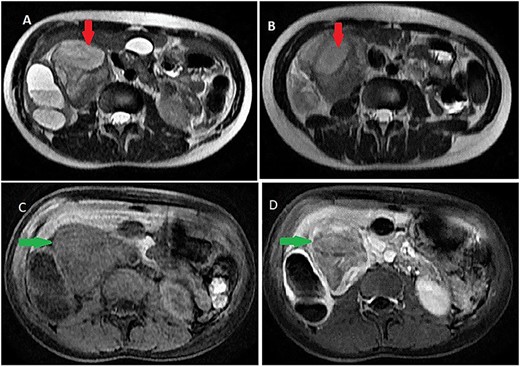

Contrast computed tomography (CT) scan revealed a voluminous (173 × 67 × 59 mm), well-limited and lobulated, right retroperitoneal tumor, hypodense, with delayed and low enhancement (Fig. 1).

Abdominal CT scan showing a retroperitoneal mass; retroperitoneal ganglioneuroma (red spark) before (A) and after (B) heterogeneous enhancement (green arrow).